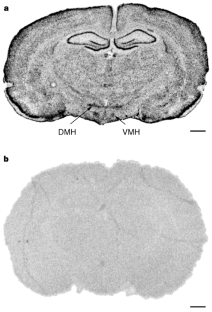

The underlying causes of obesity are poorly understood but probably involve complex interactions between many neurotransmitter and neuropeptide systems involved in the regulation of food intake and energy balance. Three pieces of evidence indicate that the neuropeptide melanin-concentrating hormone (MCH) is an important component of this system. First, MCH stimulates feeding when injected directly into rat brains1,2; second, the messenger RNA for the MCH precursor is upregulated in the hypothalamus of genetically obese mice and in fasted animals1; and third, mice lacking MCH eat less and are lean3. MCH antagonists might, therefore, provide a treatment for obesity. However, the development of such molecules has been hampered because the identity of the MCH receptor has been unknown until now. Here we show that the 353-amino-acid human orphan G-protein-coupled receptor SLC-1 (ref. 4) expressed in HEK293 cells binds MCH with sub-nanomolar affinity, and is stimulated by MCH to mobilize intracellular Ca2+ and reduce forskolin-elevated cyclic AMP levels. We also show that SLC-1 messenger RNA and protein is expressed in the ventromedial and dorsomedial nuclei of the hypothalamus, consistent with a role for SLC-1 in mediating the effects of MCH on feeding.